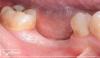

2. Мостовидный протез в боковом отделе нижней челюсти. Пациентка 43 лет. Неудовлетворительная гигиена полости рта. Имплантаты установлены в позиции зубов 35, 37.

3. Шинированные коронки в боковом отделе нижней челюсти. Пациентка 45 лет. Имплантаты установлены в позиции зубов 35, 36.